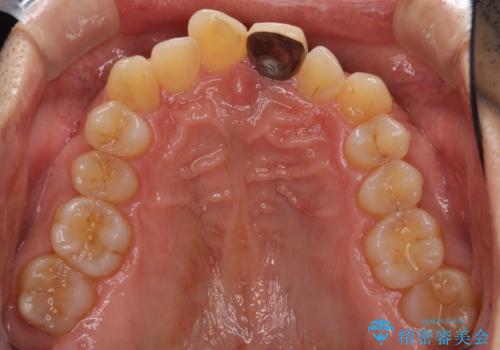

- 上下前歯のデコボコと下顎小臼歯の欠損によるスペースを気にして来院された患者様です。

下顎は左右1本ずつ小臼歯が欠損しており、右側にはやや大きな欠損がありました。

欠損により下顎歯列は相対的に小さく、上顎に深く咬みこんでしまうディープバイトとなっていました。

インビザラインによる治療を希望されたため、左側のスペースは閉じ、右側はスペースをより拡大し、インプラント補綴を行うこととしました。